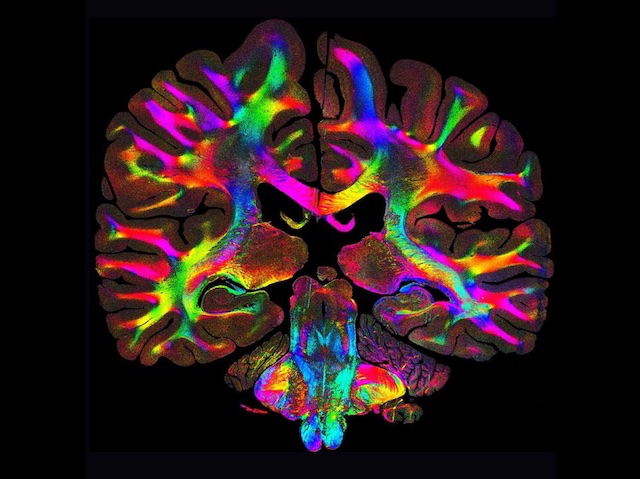

Untangling an infernal cable nest growing at the bottom of your drawer would be simpler if each wire were coloured according to its location in the mess. That's the thinking behind a new low-cost microscopy method that maps the orientation of biological fibres (such as those of nerves, collagen and muscle) at the micrometre resolution (that’s about one hundredth the width of a piece of paper). By shining light at a sample and analysing how it scatters, Computational Scattered Light Imaging (ComSLI) detects and maps fibre directions even when multiple strands cross at a single point (pictured, applied to a whole brain slice and coloured according to the orientation of nerve fibres in any spot, such as red for left-to-right or light blue running up and down). It works no matter how the sample is prepared, making it a versatile tool, and has already been used to identify structural changes in conditions such as Alzheimer’s and multiple sclerosis.